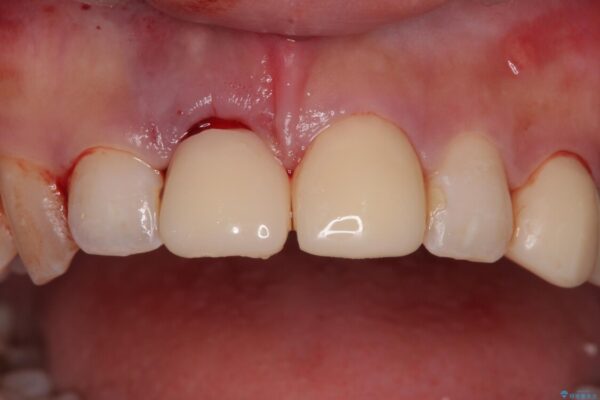

▶右上中切歯

抜歯後、即時インプラント埋入

審美性を考慮し、仮歯を即日装着

治療期間を最小限に抑えつつ、自然な前歯のラインと歯ぐきの形を維持

治療途中

• 「抜歯してブリッジ」と言われた20代女性が選んだ治療とは|たった4か月で自然な笑顔に抜歯即時インプラント+審美補綴の症例 治療途中画像